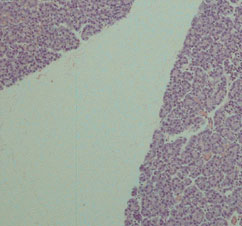

Case 2:

Haematoxylin & Eosin (x100)